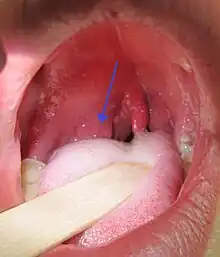

| Right sided peritonsillar abscess | |

Physical signs of a peritonsillar abscess include redness and swelling in the tonsillar area of the affected side and swelling of the jugulodigastric lymph nodes. The uvula may be displaced towards the unaffected side.[3]

Unlike tonsillitis, which is more common in children, PTA has a more even age spread, from children to adults. Symptoms start appearing two to eight days before the formation of an abscess. A progressively severe sore throat on one side and pain during swallowing (odynophagia) usually are the earliest symptoms. As the abscess develops, persistent pain in the peritonsillar area, fever, a general sense of feeling unwell, headache, and a distortion of vowels informally known as "hot potato voice" may appear. Neck pain associated with tender, swollen lymph nodes, referred ear pain and foul breath are also common. While these signs may be present in tonsillitis itself, a PTA should be specifically considered if there is limited ability to open the mouth (trismus).[3]